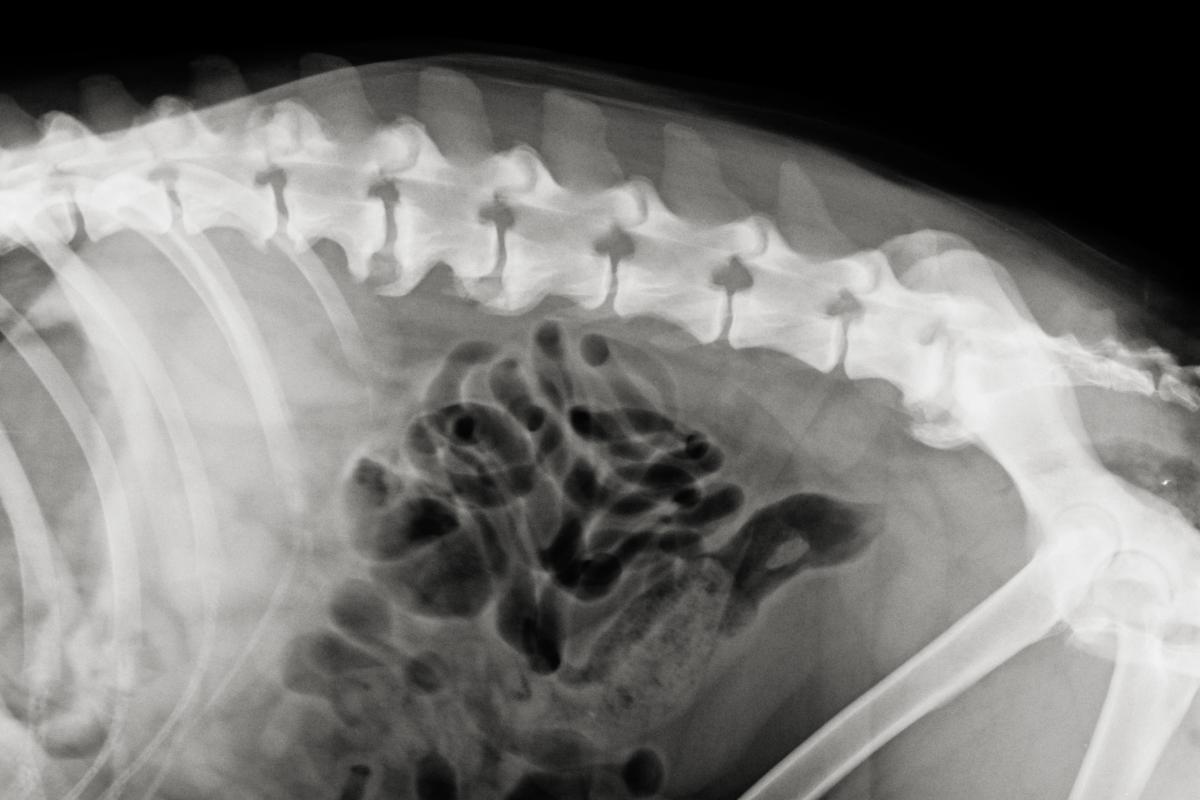

Discoespondilosis

Es una patología degenerativa del esqueleto, donde las vertebras se degeneran y comienzan a unirse unas a otras mediante el crecimiento de lo que se llaman "picos de loro"; suele tener origen bacteriano o fúngico. Esta degeneración provoca rigidez en el dorso y en ocasiones atrapa o inflama los nervios, provocando ataxia (descoordinación de la marcha), siendo típico también que el can arrastre los dedos por el suelo al andar o le fallen las patas traseras.

Tratamiento

El tratamiento es sintomático, ya que no existe cura. Así, los síntomas pueden aliviarse algo mediante corticoides y un adecuado programa de rehabilitación. Hablamos de ello aquí: "Espondilosis en perros - Síntomas y tratamiento".